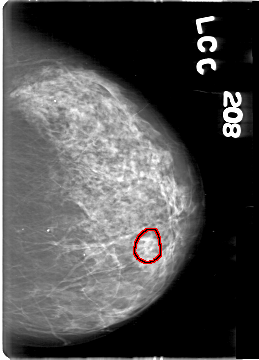

D_4164_1.LEFT_MLO

D_4164_1.LEFT_CC

LEFT_CC LINES 5386 PIXELS_PER_LINE 3871 BITS_PER_PIXEL 12 RESOLUTION 43.5 OVERLAY

LEFT_MLO LINES 5386 PIXELS_PER_LINE 3676 BITS_PER_PIXEL 12 RESOLUTION 43.5 OVERLAY

FILE: D_4164_1.LEFT_MLO.OVERLAY

TOTAL_ABNORMALITIES 1

ABNORMALITY 1

LESION_TYPE CALCIFICATION TYPE AMORPHOUS DISTRIBUTION CLUSTERED

ASSESSMENT 0

SUBTLETY 3

PATHOLOGY BENIGN

TOTAL_OUTLINES 1

BOUNDARY

FILE: D_4164_1.LEFT_CC.OVERLAY